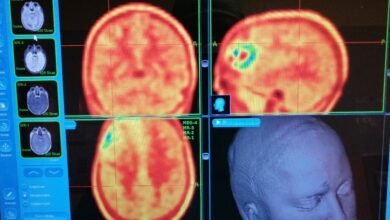

Metodica innovativa per l’asportazione di tumori cerebrali. Neurochirurgia di Careggi e Medicina Nucleare di Prato

Si chiama chirurgia biomolecolare la metodica innovativa per il trattamento del glioma cerebrale, un tumore che coinvolge il sistema nervoso…